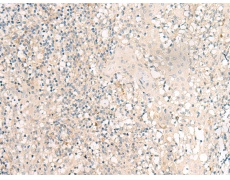

IHC positive control: |

Human tonsil |

IHC Recommend dilution: |

25-100 |